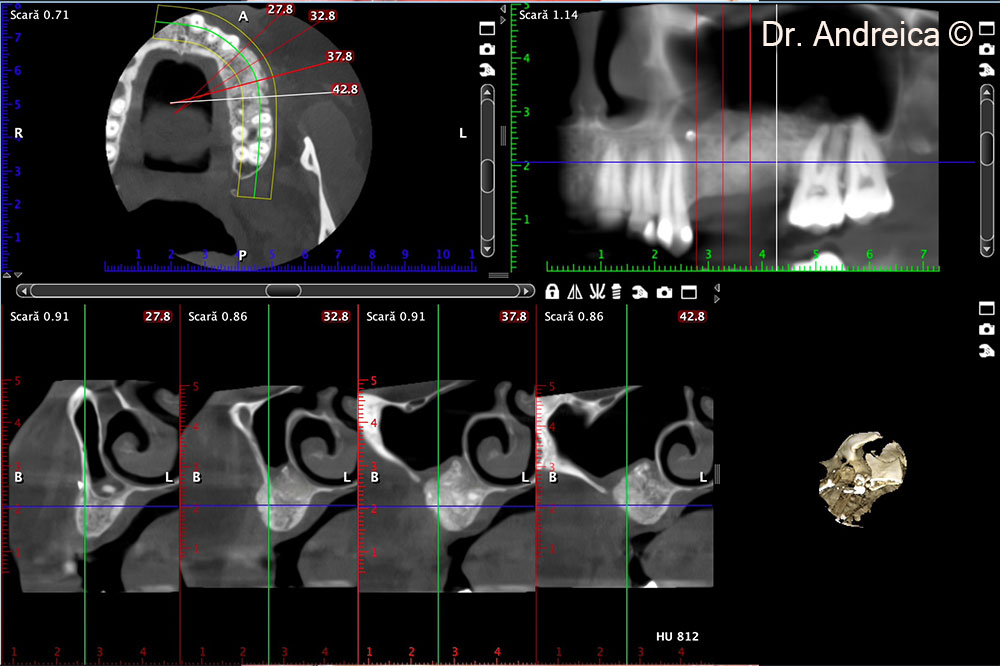

CBCT scan 5 months after surgery revealing the amount of bone that was augmented